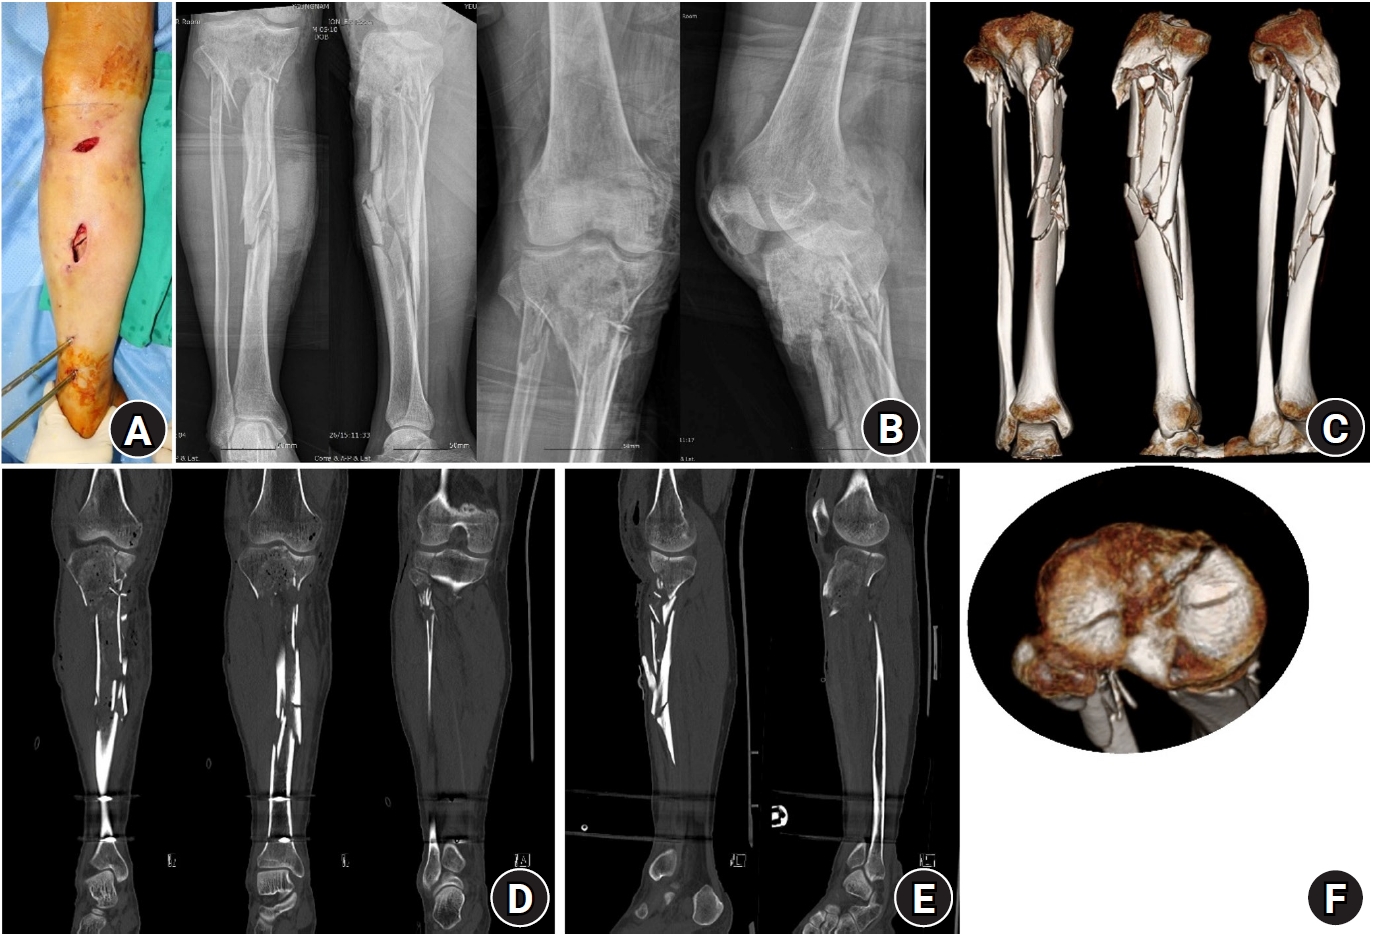

Usefulness of Computed Tomography on Distal Tibia Intra-Articular Fracture Associated with Spiral Tibia Shaft Fracture

Seong Eun Byun, Sang June Lee, Uk Kim, Young Rak Choi, Soo Hong Han, Byong Guk Kim

J Korean Fract Soc 2016;29(2):114-120.   Published online April 30, 2016

DOI: https://doi.org/10.12671/jkfs.2016.29.2.114

AbstractAbstract PDF

PURPOSE

The purpose of this study is to evaluate the usefulness of computed tomography (CT) for spiral tibia shaft fracture by analyzing associated distal tibia intra-articular fractures diagnosed by CT only which met the indication of surgical fixation and were fixed.

MATERIALS AND METHODS

Ninety-five spiral tibia shaft fractures with preoperative ankle plain radiographs and CT were analyzed retrospectively. The incidence and type of associated distal tibia articular fractures were evaluated by reviewing ankle plain radiography and CT. The number of fractures diagnosed by CT that correspond with the indication of fixation and that were actually fixed were analyzed.

RESULTS

Among 95 spiral tibia shaft fractures, 62 cases (65.3%) were associated with distal tibia intra-articular fracture. There were 37 cases of posterior malleolar fracture, 5 cases of avulsion fracture of the distal anterior tibiofibular ligament, 5 cases of medial malleolar fracture, and 15 cases of complex fracture. Among 52 posterior malleolar fractures including complex fracture, 20 cases were diagnosed by ankle plain radiograph. Of these 20 cases, 16 posterior malleolar fractures (80.0%) met the indication of surgical fixation, and 14 cases were actually fixed with a screw. Among 32 posterior malleolar fractures diagnosed by CT only, 26 cases (81.3%) met the indication of surgical fixation and 18 cases (56.3%) were fixed by screw.

CONCLUSION

Approximately 50% of associated fractures were diagnosed by CT only and more than 80% of associated posterior malleolar fractures met the indication of surgical fixation and among these fractures, 18 cases (56.3%) were actually fixed by screw. This result suggests that CT is useful in diagnosis and treatment of distal tibia intra-articular fracture associated with spiral tibia shaft fracture.